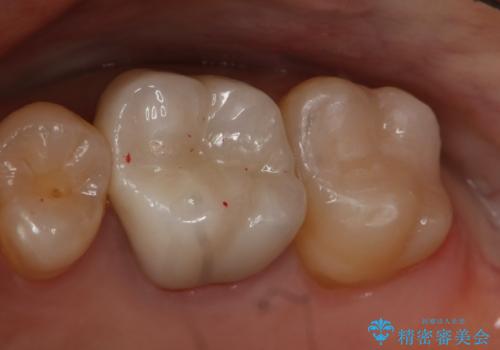

- 右上6番の銀歯をセラミックに変えたいと希望された患者様です。

切削量、形態を考慮し、セラミックインレーでの治療を計画しました。

銀歯と虫歯を除去した上でCRで裏層し形態を整えて印象を行っています。